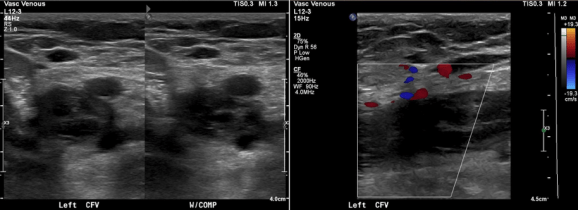

Completion venography suggested successful iliocaval recanalization and revascularization but these procedures are not done without a final intravascular ultrasound (IVUS).

Intravascular ultrasound revealed incomplete expansion of the right common femoral stent. This was treated with another stent and ballooning with the result on the right.

Venography alone is insufficient in determining patency. As illustrated, IVUS ensures a durable outcome.

The patient is a young woman who three weeks prior to presentation developed sudden low back pain and left leg pain while exercising on an elliptical. This pain worsened through the subsequent weeks and she developed fevers, chills, and night sweats, and she came to the emergency department. There, she was found to have left thigh and leg swelling. Duplex revealed a left iliofemoral DVT starting from the iliocaval tributary and extending to her left femoral vein (figure above). A CT scan revealed a pulmonary embolism to the left lung (below). No precipitating factors were present. Vascular surgery was consulted.